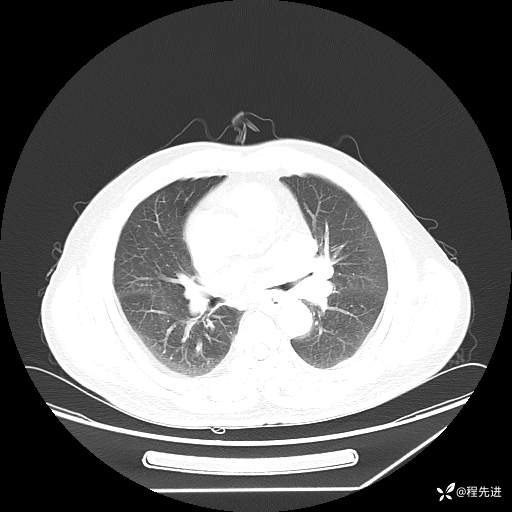

患者性别:男

患者年龄:57岁

简要病史:声嘶2月余

CT平扫+增强: